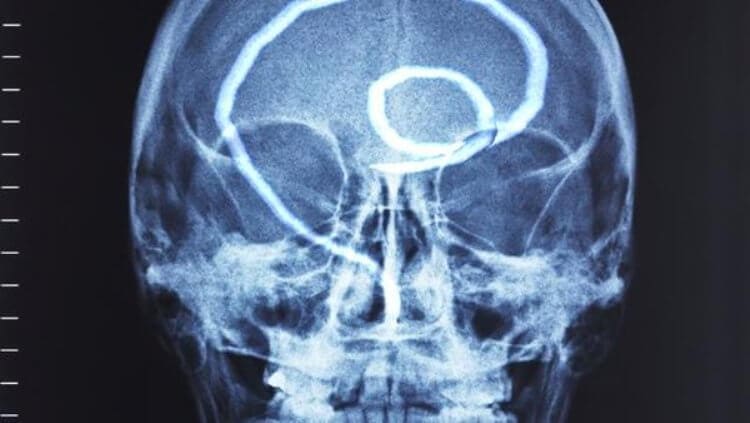

Drugi čest slučaj je infekcija ljudskog mozga. To dovodi do poremećaja funkcija, razdražljivost, umor i nagle promjene raspoloženja. I unutra u kasnijoj fazi, kako se mozak puni parazitima, razvijaju se neke ozbiljnije bolesti i to dovodi do smrti.

“Imamo arhivu fotografija: fotografije snimljene tokom obdukcije kada otkrijemo različite parazite u organima tijela. Evo nekoliko primjera. Ali upozoravam vas, oni su užasni. »